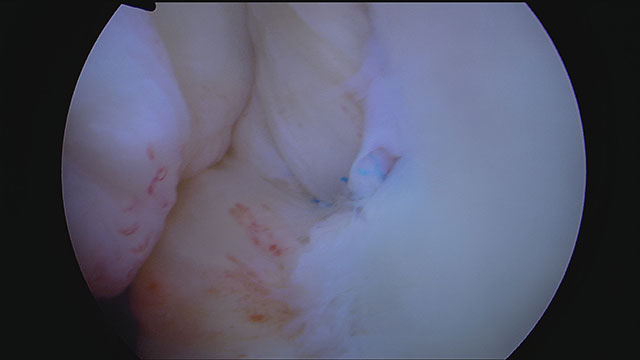

Endergebnis der Schulterstabilisierung. Das Labrum und Teile der Kapsel sind wieder fest am vorderen Pfannenrand fixiert. Gut zu erkennen ist der Wulst des Labrums und die Kapselraffung, die das Volumen im vorderen Gelenkraum verkleinert.